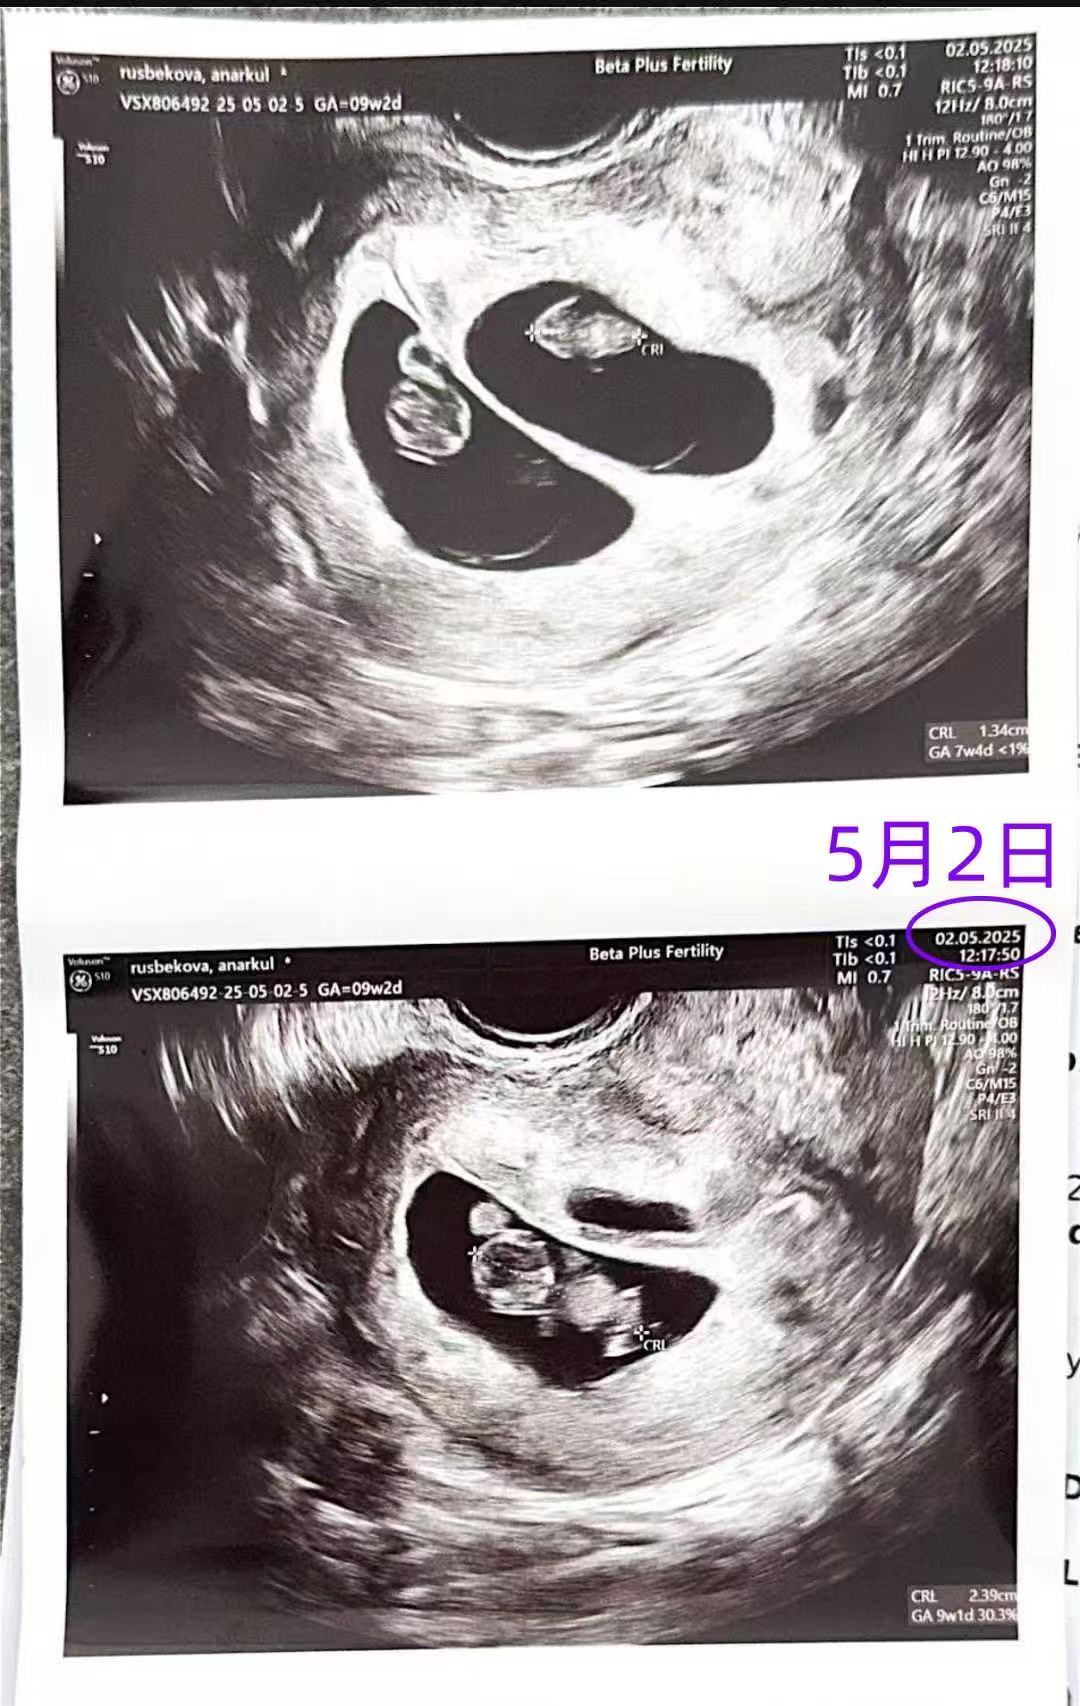

格鲁吉亚代孕代母9周产检顺利过关

发表日期:2025-5-2

格鲁吉亚爱缘好孕恩泽代孕代母5月2日9周检查顺利通过。

格鲁吉亚爱缘好孕恩泽代孕代母5月2日9周检查顺利通过。